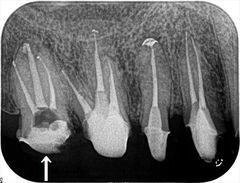

根管治療広島

右上第二大臼歯の再根管治療を終えました。2018.03.09